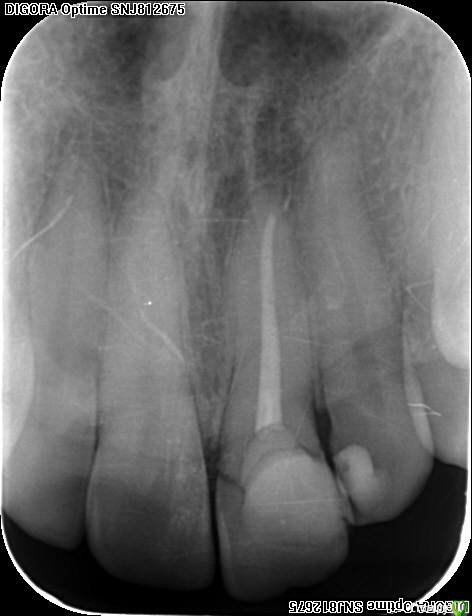

an_ver Опубликовано 15 декабря, 2015 Поделиться Опубликовано 15 декабря, 2015 Травма 21, немного сместился,удаление,имплантация SPI 4.2*13,ГенОсс+ ауто со сверла,для временной коронки использован свой зуб)),немного укоротили реж.край,чтоб не травмировать,унифлекс 5/0 18 Ссылка на комментарий